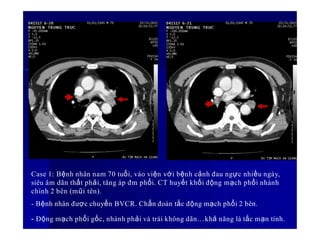

Case 1: Bệnh nhân nam 70 tuổi, vào viện với bệnh cảnh đau ngực nhiều ngày,

siêu âm dãn thất phải, tăng áp đm phổi. CT huyết khối động mạch phổi nhánh

chính 2 bên (mũi tên).

- Bệnh nhân được chuyển BVCR. Chẩn đoán tắc động mạch phổi 2 bên.

57

- Động mạch phổi gốc, nhánh phải và trái không dãn…khả năng là tắc mạn tính.

Đm phổi gốc Đm chủ